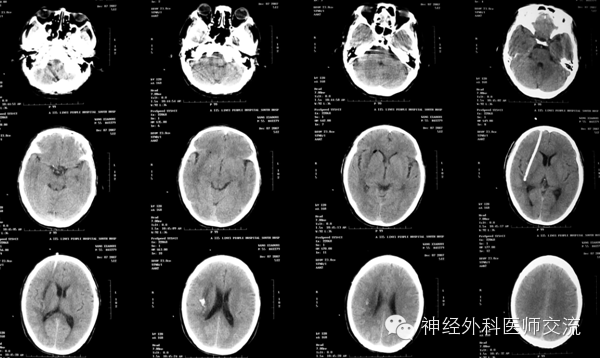

再来个延迟手术病例,这个病人开始不需要做,但是年轻人,反应重

一、 壳核出血

壳核出血占高血压脑出血的50%以上,积极完善地救治壳核出血对于降低脑出血的病死率,提高患者的生活质量具有重要意义。

(2)CT图片处理——穿刺点的选择及介入手术入路

① 确定穿刺平面:据CT所显示的血肿,选择血肿最大断层,即为要穿刺的平面,也就是说:操作时要将引流导管沿着这一血肿最大层面进入血肿腔内。确定该层面至颅底层面的距离(即厚度)(X毫米:一般为50~60 mm)。

② 确定穿刺点:在血肿的最大层面上划出血肿的最大长轴线,与前额头皮的交点即为理论穿刺点,测出该点至血肿远端的距离(毫米),该数值减去5mm~10mm即为置管深度,一般为80~120mm。

确定实际穿刺点要做到两个避开:避开额窦、避开上矢状窦!实际穿刺点,一般为正中矢状线旁开15mm~20mm,内眦上方45mm~60mm的前额之交点,多为55mm。